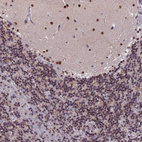

Immunohistochemical staining of human cerebellum shows strong nuclear positivity in cells in molecular layer.